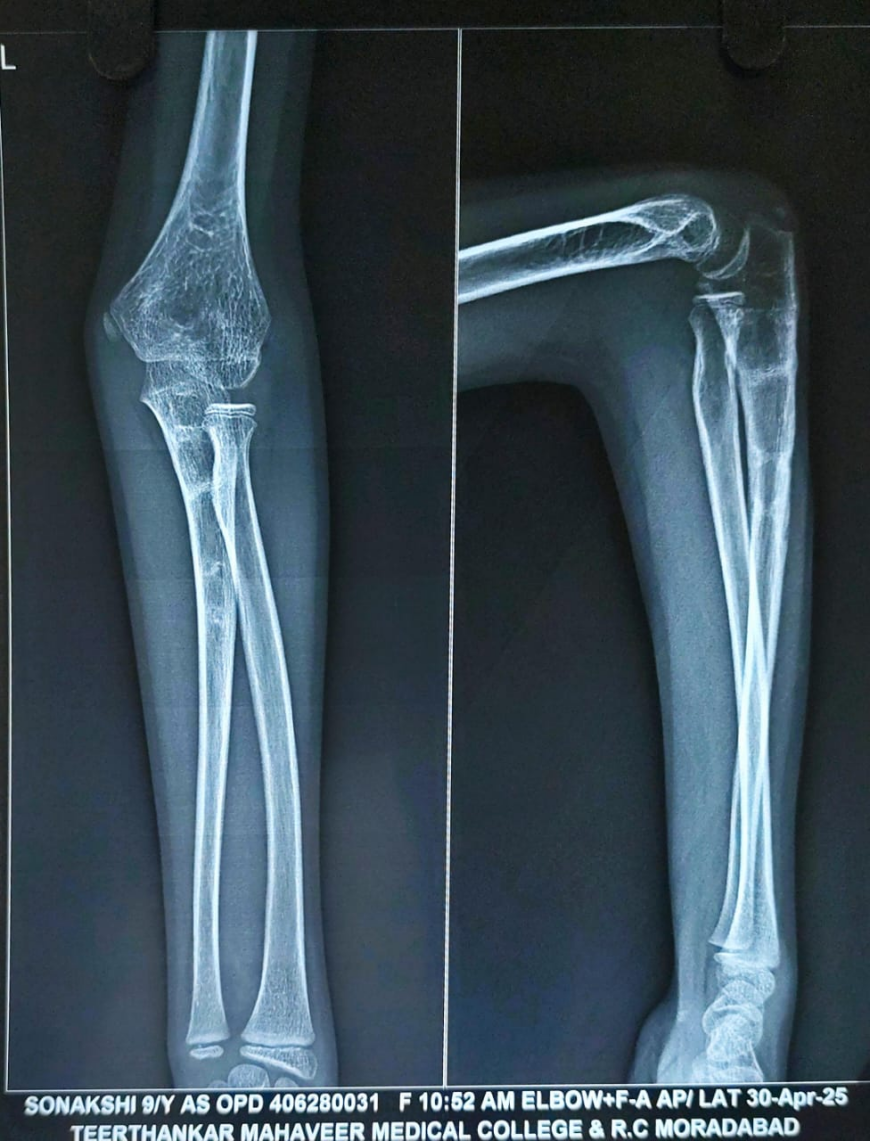

By the 9-month follow-up, radiographs confirmed complete union of the osteotomized ulna, and the radial head remained in a reduced, anatomical position. To prevent any implant-related complications, implant removal was done at 9 months (Fig. 8).

Figure 8: X-ray after implant removal.

At the time of the past follow-up at 15 months, the X-ray demonstrated a well-maintained reduction of the radial head with congruent radiocapitellar alignment. The ulna showed complete union with satisfactory remodeling. There was no evidence of implant-related complications, re-dislocation, or deformity (Fig. 9). The child had regained a full, pain-free range of motion in the left elbow, including full flexion, extension, pronation, and supination (Fig. 10a, b, c, d). There were no signs of instability or functional limitations in daily activities. Almost complete recovery of PIN palsy was obtained. At the 15-month follow-up, physeal growth disturbance and angular deformities were evaluated and not observed. The patient achieved an excellent outcome as per the Mayo Elbow performance score.

Figure 9: Follow-up radiograph at 15 months after surgery. The image shows maintained reduction of the radial head with congruent radiocapitellar alignment, complete union and remodelling of the ulna, and absence of implant-related complications or re-dislocation.